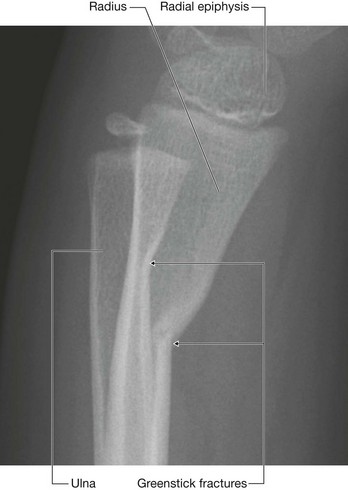

In the clinic Bone fractures

Fractures occur in normal bone because of abnormal load or stress, in which the bone gives way. Fractures may also occur in bone that is of poor quality (osteoporosis); in such cases a normal stress is placed upon a bone that is not of sufficient quality to withstand this force and subsequently fractures.

In children whose bones are still developing, fractures may occur across the growth plate or across the shaft. These shaft fractures typically involve partial cortical disruption, similar to breaking a branch of a young tree; hence they are termed “greenstick” fractures (Fig. 1.15).

image

Fig. 1.15 Radiograph, lateral view, showing greenstick fractures of the distal radius and distal ulna.